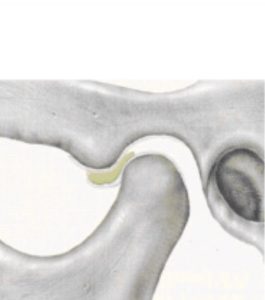

関節円板が前方にズレていて、変形してる状態。

口を開けると、下顎頭が変形した関節円板に引っかかる。

引っ掛かりが外れて下顎頭がさらに前に出るときに、カックンと音が鳴る。